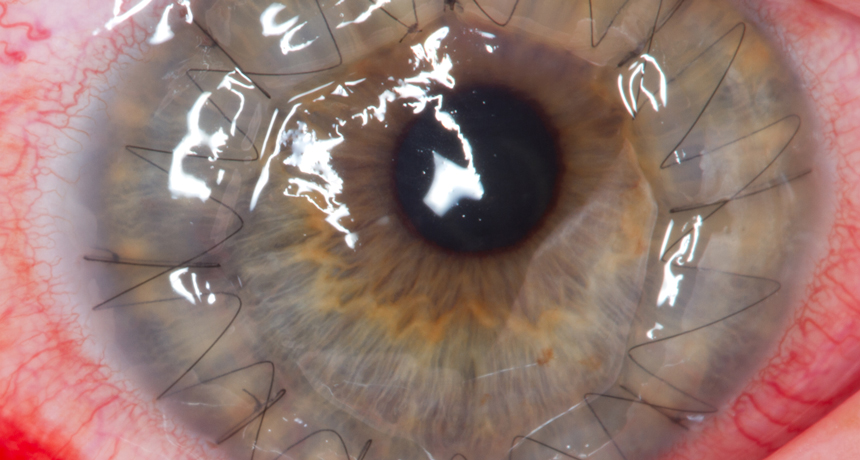

EYE OPENER  Women who receieve corneal transplants are more likely to reject them if their donors are male.

Megor1/Wikimedia Commons (CC BY-SA 3.0)